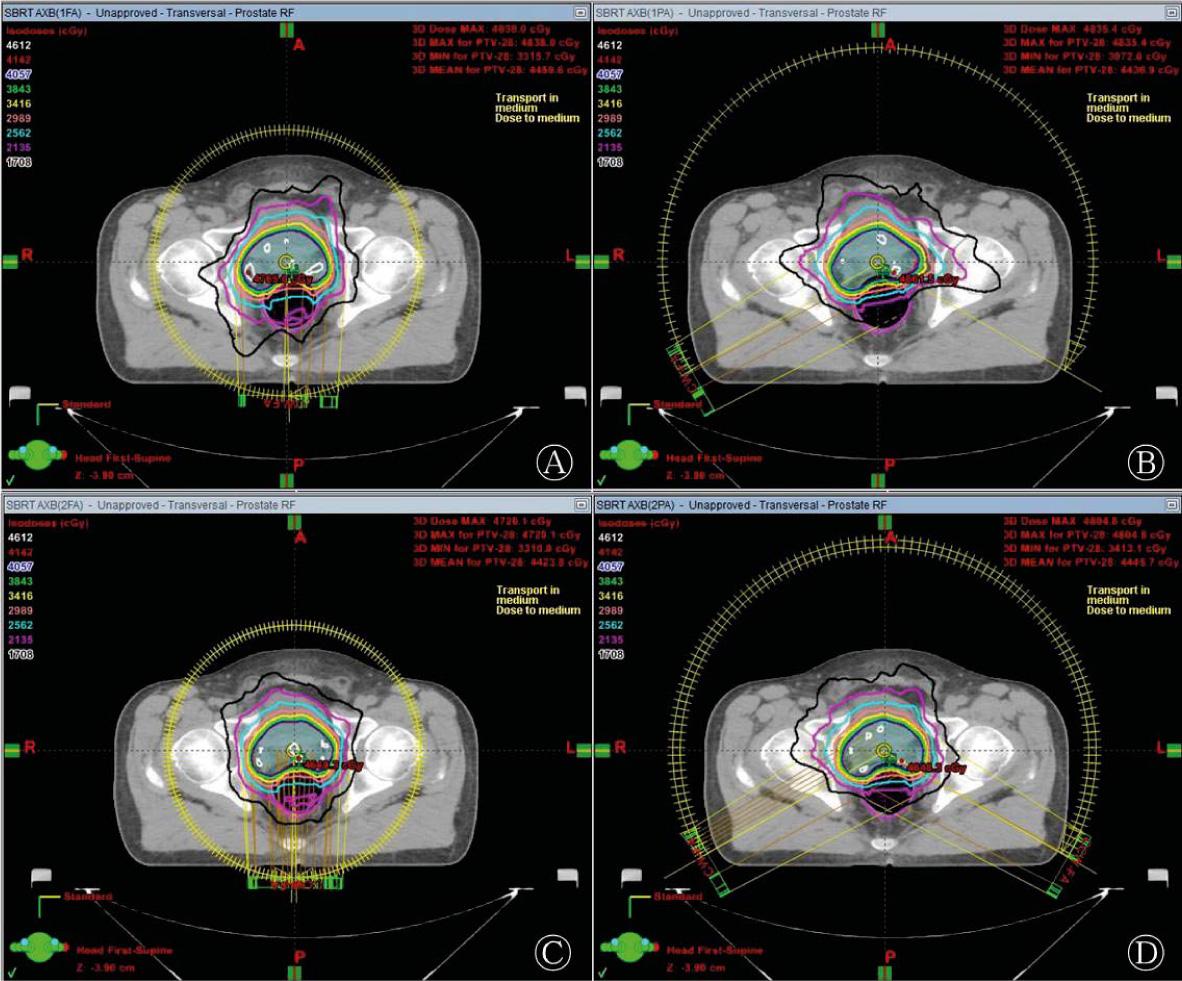

Average monitor unit and delivery time for prostate SBRT-VMAT plans using four arc arrangements_

| Beams | 1FA (Mean ± SD) | 1PA (Mean ± SD) | 2FA (Mean ± SD) | 2PA (Mean ± SD) |

|---|---|---|---|---|

| MU | 1575±63 | 1627±56 | 1646±97 | 1660±98 |

| Delivery time (min) | 1.01±0.02 | 0.69±0.01 | 2.00±0.01 | 1.36±0.02 |